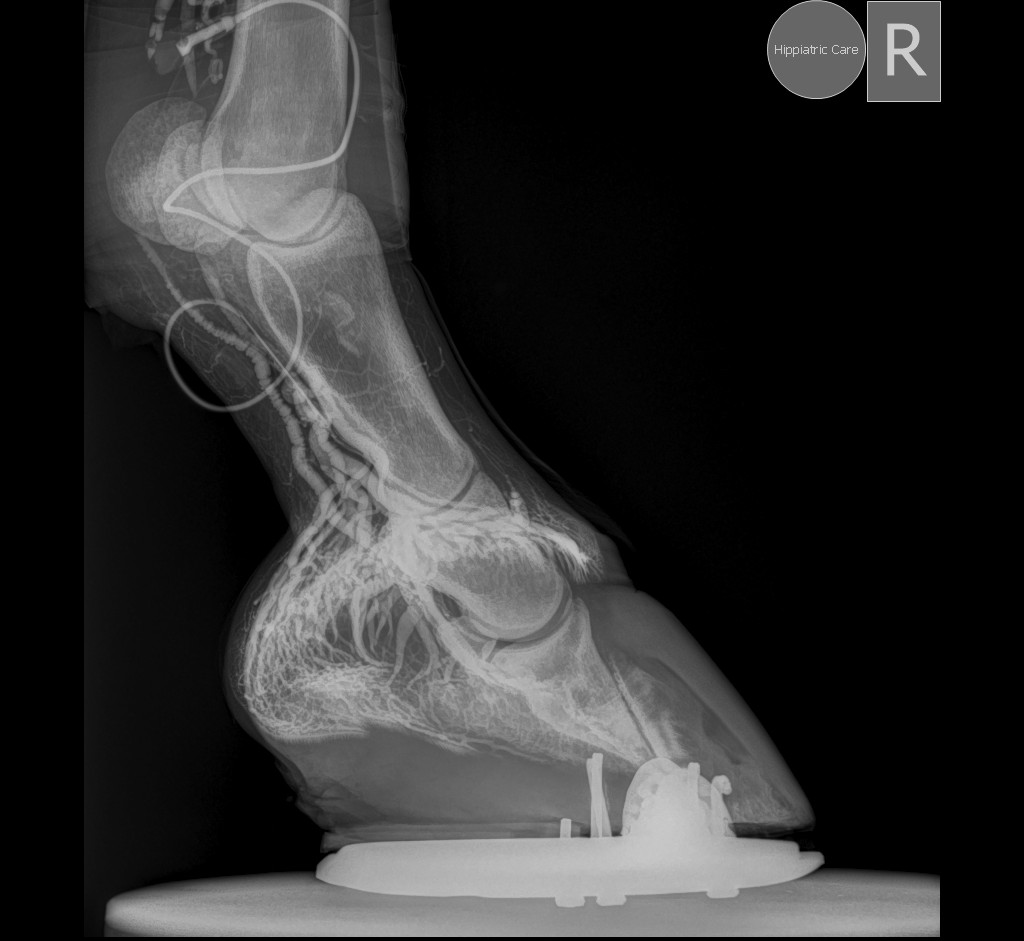

Η φλεβογραφία αποτελεί ένα ιδιαίτερα χρήσιμο εργαλείο για τη διάγνωση και θεραπεία της ενδονυχίτιδας, καθώς επιτρέπει την εκτίμηση της αγγειακής βλάβης εντός της οπλής πριν από την εμφάνιση αλλοιώσεων στις συμβατικές ακτινογραφίες. Η αξία της είναι μεγαλύτερη όταν εφαρμόζεται κατά την έναρξη της νόσου, διότι αποκαλύπτει τον βαθμό της ήδη εγκατεστημένης αγγειακής βλάβης και συμβάλλει στον καθορισμό της κατάλληλης θεραπευτικής στρατηγικής.